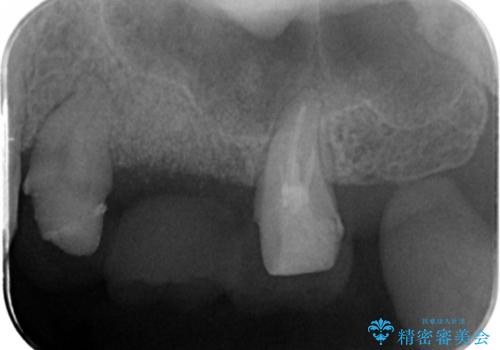

- 左上奥歯の違和感の改善を求めて来院されました。

詳しく診査したところ、歯の破折が認められたため抜歯が必要な状態です。

抜歯時に骨移植材を填入することで、抜歯後に大きく歯ぐきのボリュームが失われることを防ぎます。